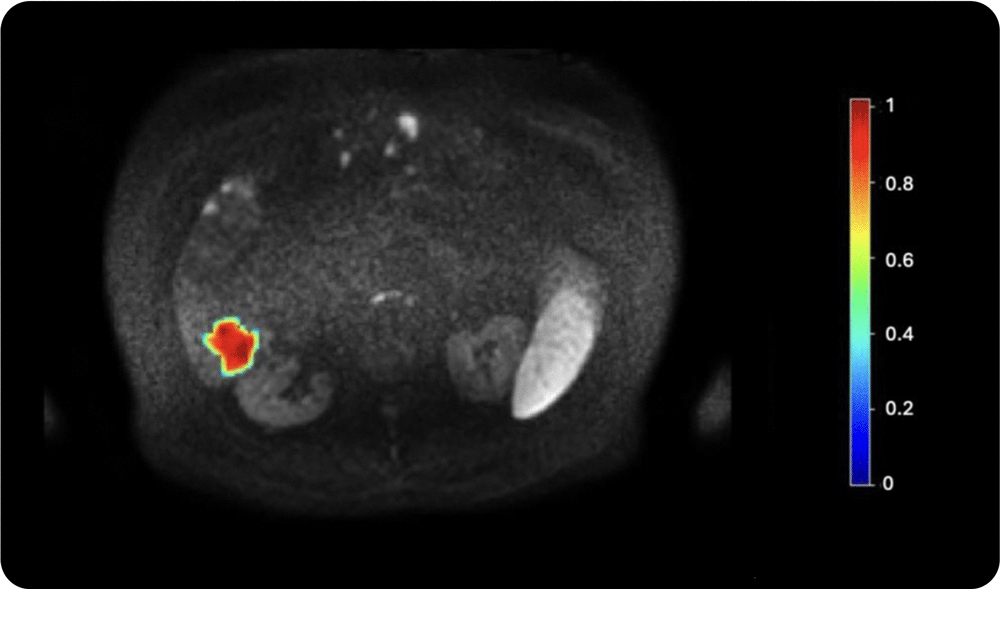

4. Tumor heterogeneity assessment

Entropy and other advanced radiomic features extracted from medical images help quantify intra-lesion variability; crucial for understanding tumor aggressiveness and predicting treatment response.

Intra-lesion heterogeneity quantified using entropy from a DWI MRI scan. Texture features reveal microscopic heterogeneity beyond visual assessment. High entropy often indicates more aggressive tumors, while low entropy suggests better treatment response. Temporal changes may serve as early biomarkers of therapeutic effect.